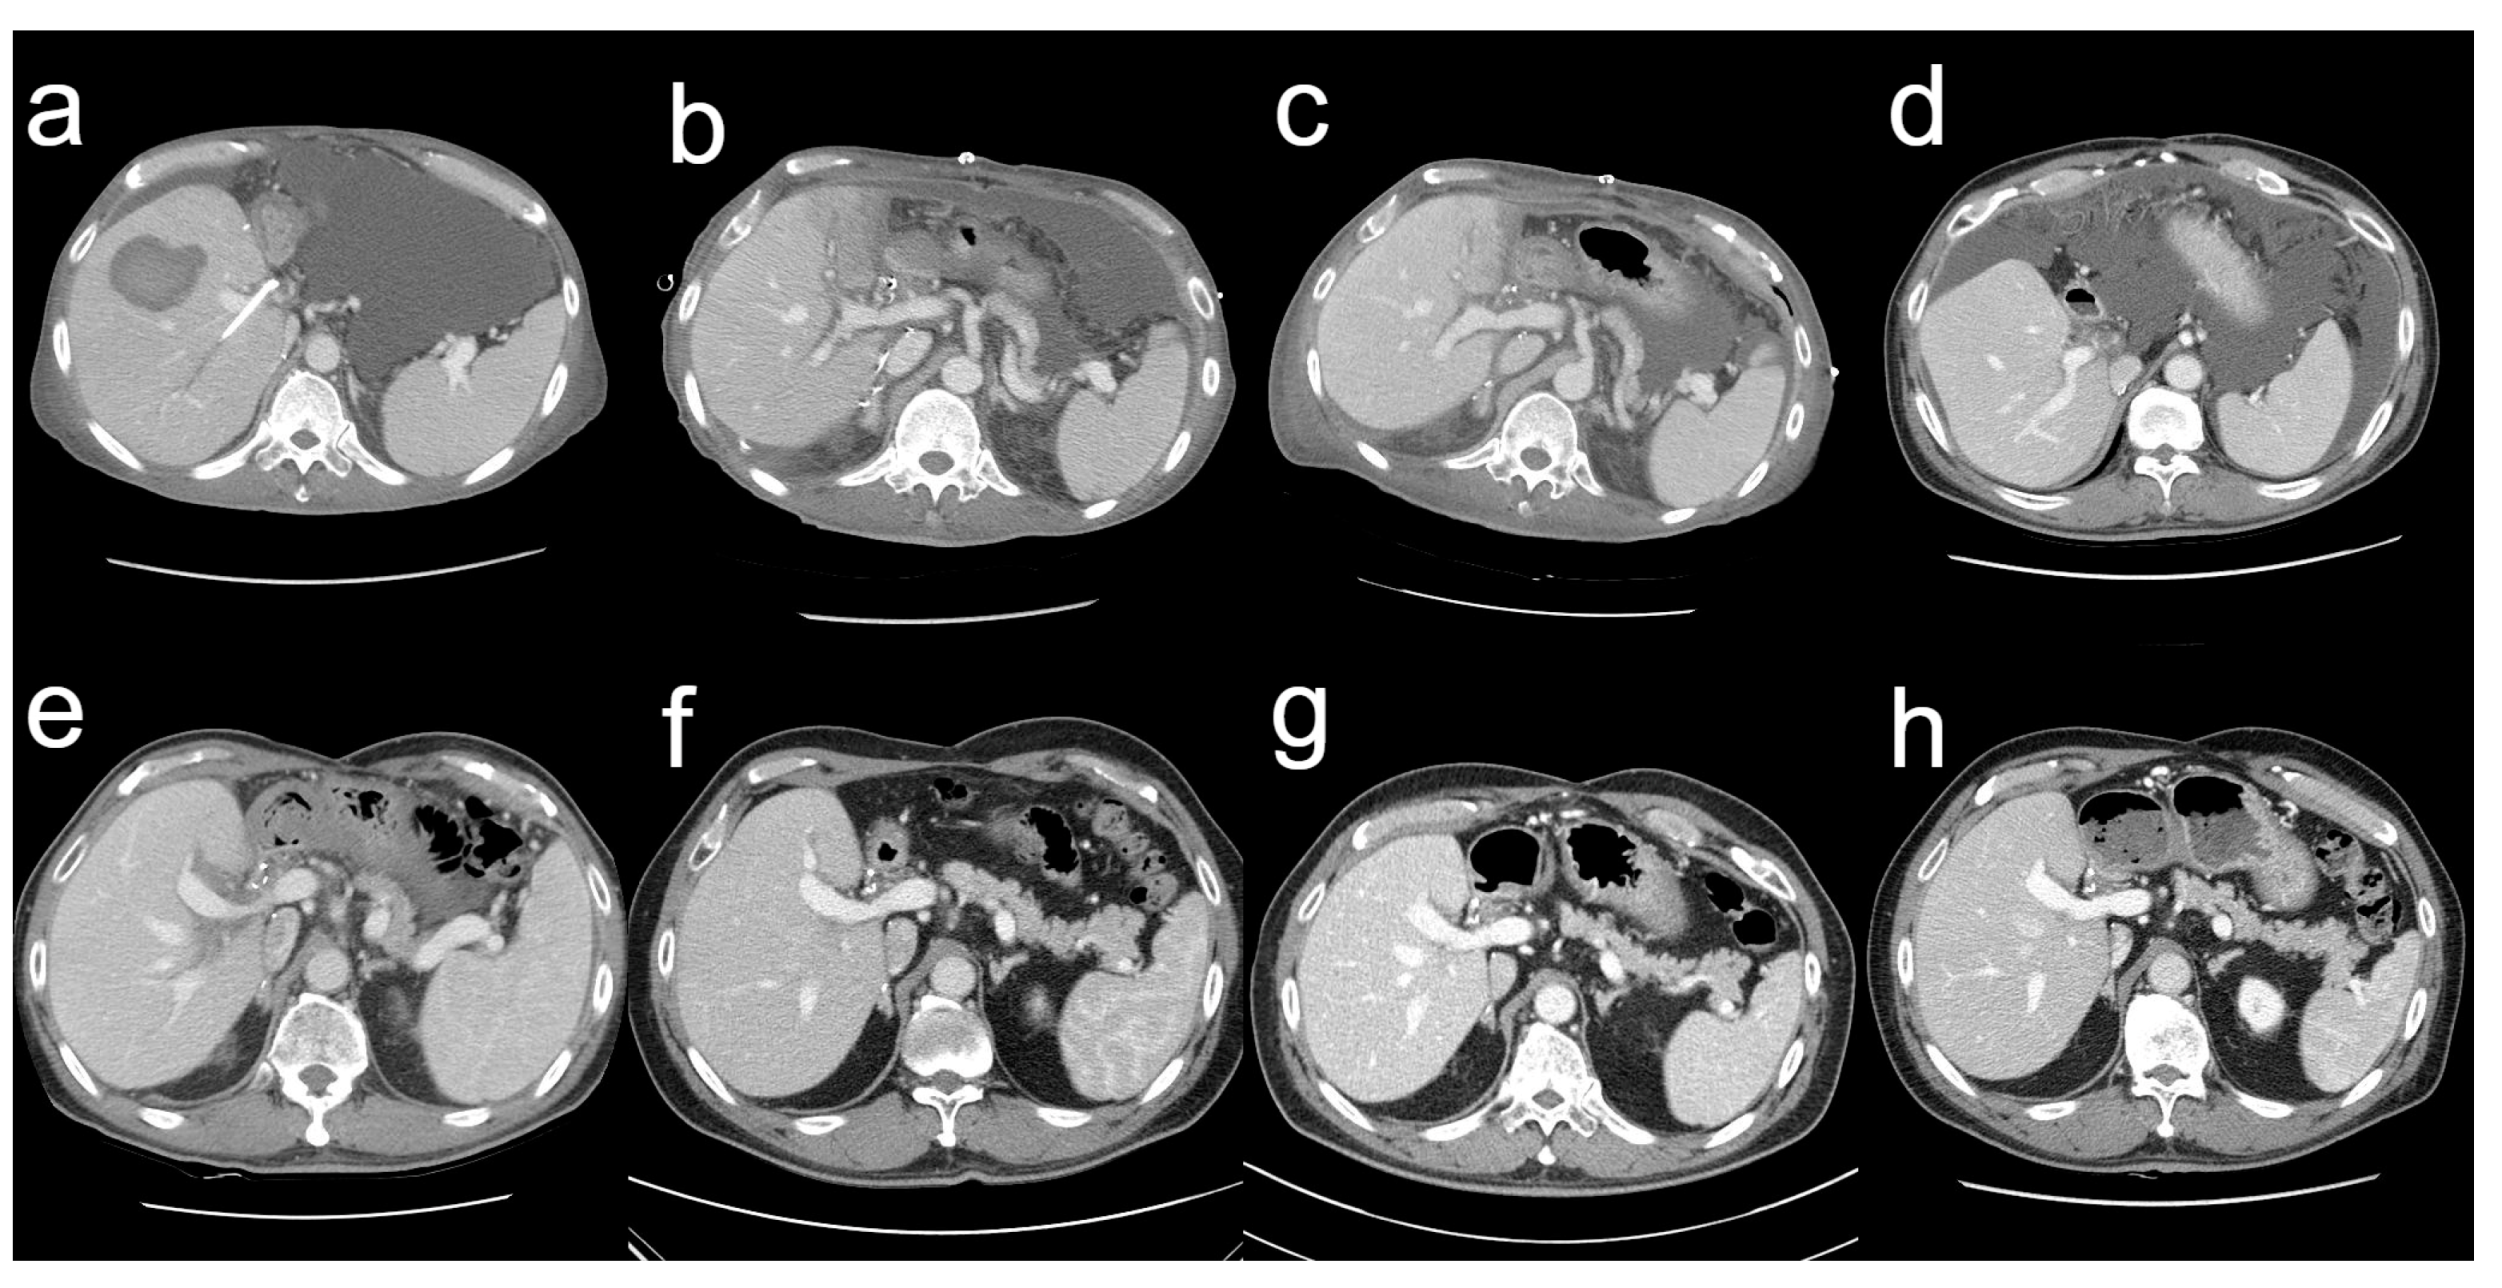

On 3 October 2014, the serum total bilirubin was 23.0 mg/dL. The abdominal CT scan revealed a parenchymal hematoma in the graft, with a stent visible in the bile duct and abundant ascites in the peritoneal cavity (Figure 3a). Additionally, the patient developed pneumonia (Figure 4a). The heart rate reached a maximum of 130 beats per minute and the body temperature rose to 38.0 °C. The respiration rate was over 30 breaths per min and the blood oxygen saturation dropped to 88%. His blood pressure dropped to 89/57 mm of mercury (mmHg). His mental status began to deteriorate. All the findings indicated shock due to sepsis. He was therefore transferred to the intensive care unit, intubated, and mechanically ventilated. Vasopressors were administered to treat low blood pressure. The cytomegalovirus (CMV) antigenemia assay showed positive results, so a preemptive intravenous injection of ganciclovir was initiated. Klebsiella pneumoniae was identified in the sputum culture and endotracheal aspirate culture, and antibiotics were initiated to treat pneumonia and sepsis. Fortunately, hemodialysis was not required; his renal function remained normal. His MELD score was 23, with a serum total bilirubin level of 29.1 mg/dL. In the state of liver failure, it was judged that pneumonia and sepsis were difficult to improve, so liver re-transplantation was seriously considered.

During the outpatient follow-up, biloma was detected 3 months after surgery (Figure 3d), and percutaneous catheter drainage and transhepatic biliary drainage were performed. The tubes were removed 10 months after surgery. Since then, the postoperative course has been event-free at regular outpatient follow-ups. The patient has, so far, had normal laboratory findings and no signs of complications.

A series of follow-up liver CT scans showed improved results with sufficient liver regeneration in the recipient (Figure 3).

Figure 3. Series CT scans on pre-retransplant day 12 (a), postoperative day 10 (b), postoperative day 28 (c), postoperative month 3 (d), postoperative year 1 (e), postoperative year 3 (f), postoperative year 5 (g), and postoperative year 8 (h).